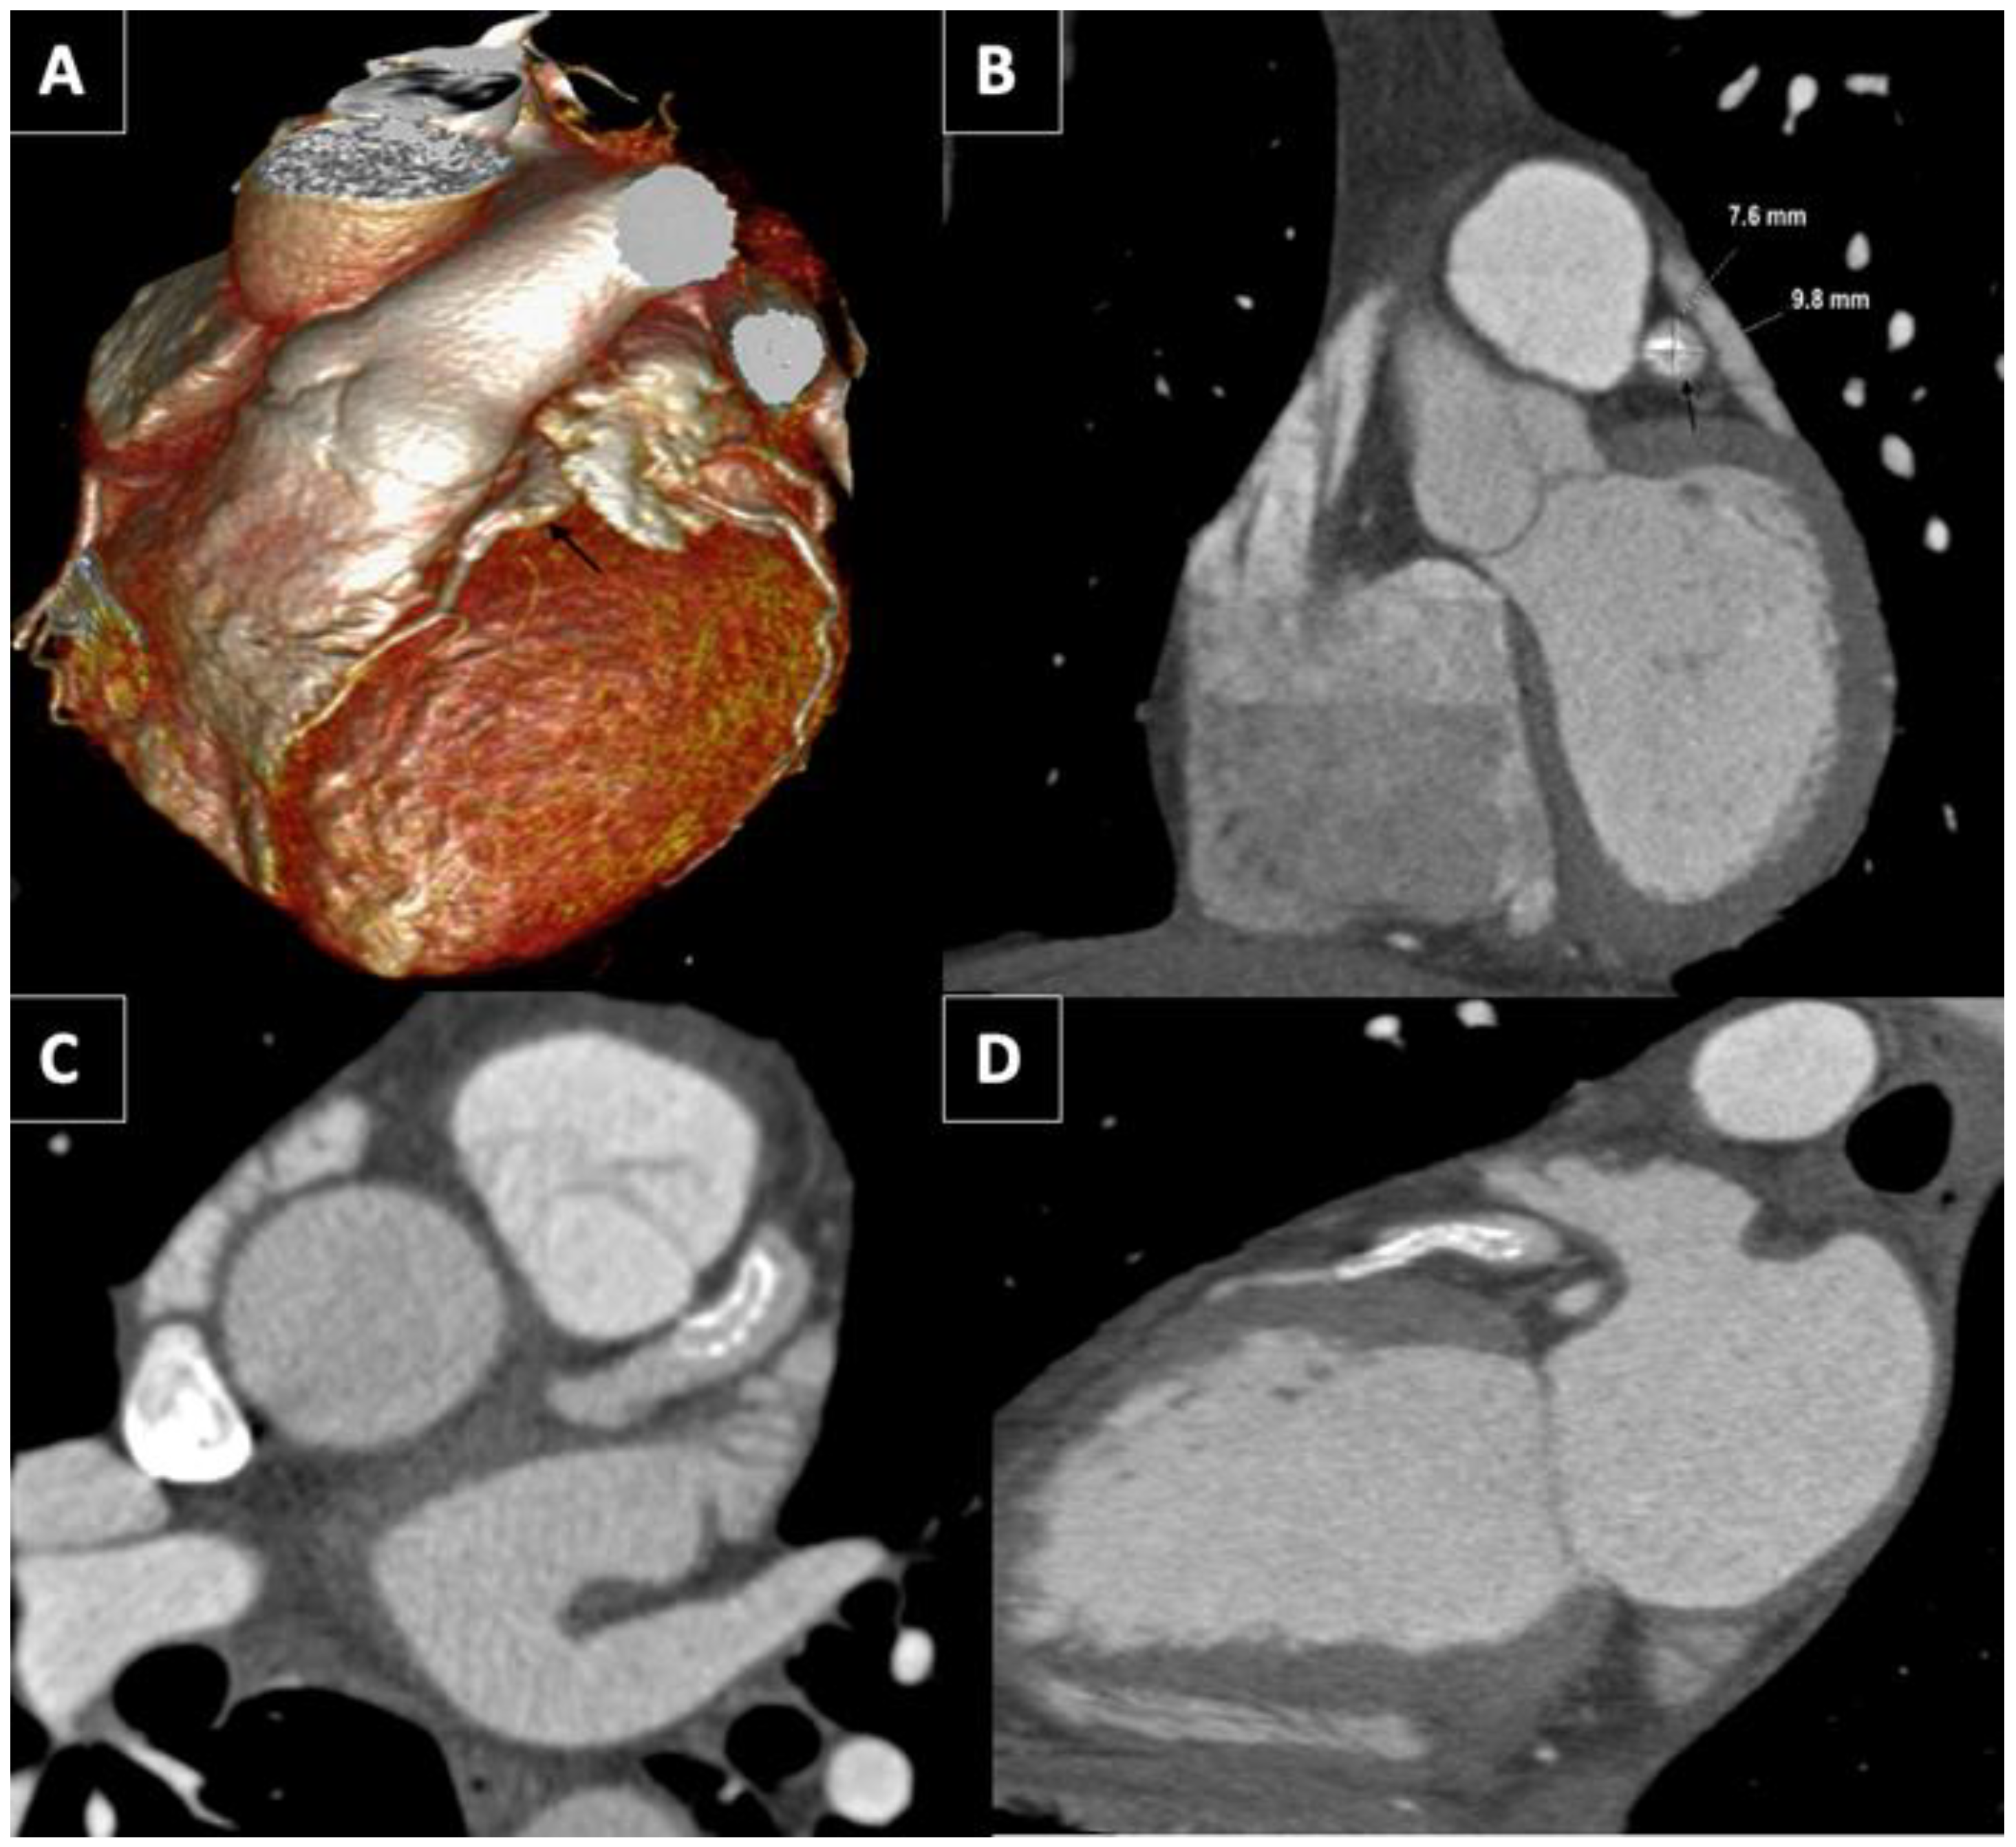

A coronary computed tomography angiography (CCTA) was carried out one year later to check the permeability of the stent. The CCTA showed a 7.6 × 9.8 mm diameter aneurysm (Figure 2A,B). The stent was “floating” in the aneurysm (Figure 2C,D) with a preserved distal flow. Acquired and congenital thrombophilia disorders were carried out. Clopidogrel was discontinued and patient agreed to be anticoagulated endlessly. The patient did not have angina two years after STEMI.

Figure 2. CCT. (A) GCA (black arrow) lateral view on three-dimensional volume-rendered CCT. (B) Coronal view of GCA (black arrow) with dimensions in CCT. Axial (C) and sagittal oblique (D) view of GCA showing the stent “floating” in the aneurysm with a “funnel”-like form disposition.